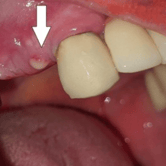

Pérdida de un diente único

La pérdida de un diente único es cuando un solo diente se ha caído o ha sido extraído, y se necesita un implante para reemplazarlo.

Los pacientes pueden notar un espacio donde solía estar el diente. Esta condición puede afectar la estética y la función masticatoria.

El tratamiento incluye la colocación de un implante dental para restaurar el diente perdido.